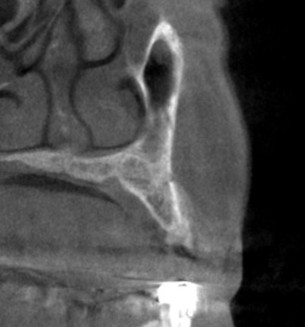

左臼歯に、3歯は必要と思われましたが、CTを見ると、1本目は骨の幅が狭く、2本目、3本目は骨の高さが足りません。

薄いところでは1mm程しかありませんでした(下の写真、2段目)。